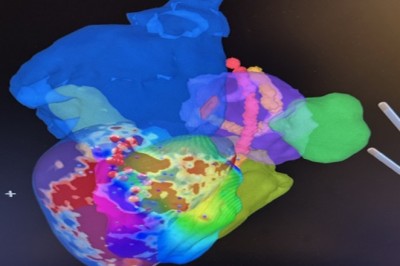

أول عملية استئصال عضلة القلب البطينية الإقفارية البشرية بنجاح في iCMR